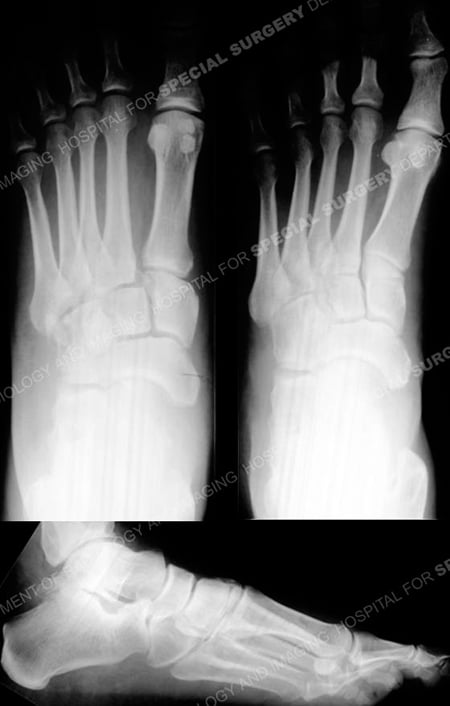

Anteroposterior, oblique, and lateral radiographs revealing a Lisfranc fracture-dislocation.